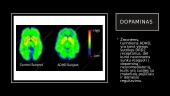

Dopaminas

• Išsiskiria didesniais kiekiais smegenyse tuomet, kai jaučiami malonūs pojūčiai

• Jis dar vadinamas laimės hormonu, nes yra atsakingas už pasitenkinimo būseną, kuri yra labai svarbi žmogaus veiklos motyvacijai, mokymuisi. Dopaminas gaminamas keliose smegenų srityse kai žmogus patiria teigiamą (subjektyviu to žmogaus vertinimu) patirtį.